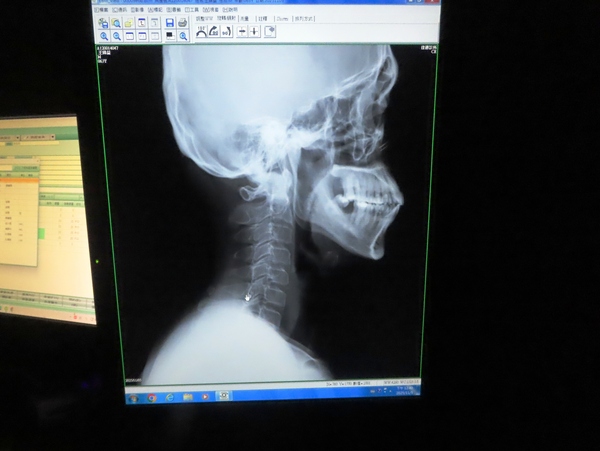

10:43 左手不能抬高,來佳德診所 (臺北市松山區健康路18號) 求診

佳德診所看診室

原來肩部活動與頸部脊椎有關

肩夾擠症候群(Shoulder Impingement Syndrome)是指當您抬高手臂時,肩膀的旋轉肌袖肌腱或肩峰下滑囊在肩峰(肩膀上方的骨頭凸起)下方被夾擠到,導致疼痛和發炎的現象。

左肩膀打了兩針 (大概是類固醇)